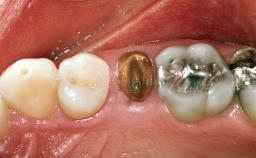

A healthy 26-year-old woman was referred for evaluation and treatment of her failing maxillary right central incisor (tooth 11). She reportedly traumatized the tooth at about age 9 and subsequently had repeated conventional and surgical endodontic procedures and fixed restorations. Despite these procedures, she had recurrent fistulas in the apical mucosa and a mid-facial pocket of 7 mm with suppuration. All other sites on the tooth probed 3 mm without inflammation. She presented with a medium biotype with triangularlyshaped teeth and a moderately high smile line, showing all of her papillas and a few millimeters of marginal gingiva in a full smile.Ceramic veneers were present on teeth 12, 21, and 22, and they were known to be somewhat bulky, eventually requiring replacement. She had a strong desire to avoid additional tooth preparation and would not consider a fixed dental prosthesis to replace tooth 11.

Case Type Single-Tooth Space

Jaw Maxilla

Area Anterior

# of Teeth 1

# of Implants 1